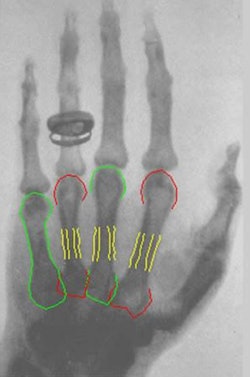

The new version "is a more powerful method for locating the bones in the image," he noted in an email to AuntMinnieEurope.com. "The previous method located only the shafts, while the new approach locates the entire contours of the four metacarpals, and it does so very robustly."

Thodberg and his team used machine learning to derive the mathematical models for the image analysis method from the shape and appearance of the bones in the Jena radiographs. They manually traced the contours of bones in 200 subjects, using an automated method to mark the contours at anatomically corresponding locations in the cohort.

This study used shape models of metacarpals 2 to 5 from patients ranging in age from 16 (girls) and 18 (boys) up to 90 years old. While reconstructing bone contours, the technique derives a "misfit" score representing a deviation of the observed image from what is expected in the trained image model. The outcome of the analysis is divided into three classes based on the misfit threshold: accepted images, questionable images, and rejected images.